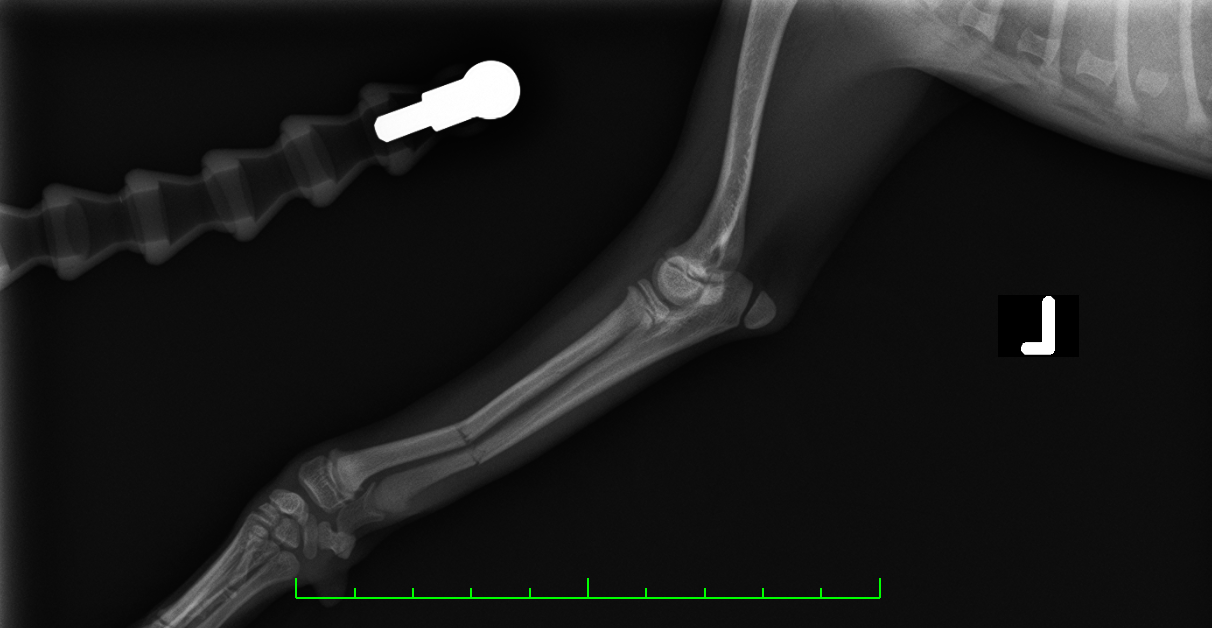

レントゲンより橈骨、尺骨の骨幹部で骨折が認められた

before